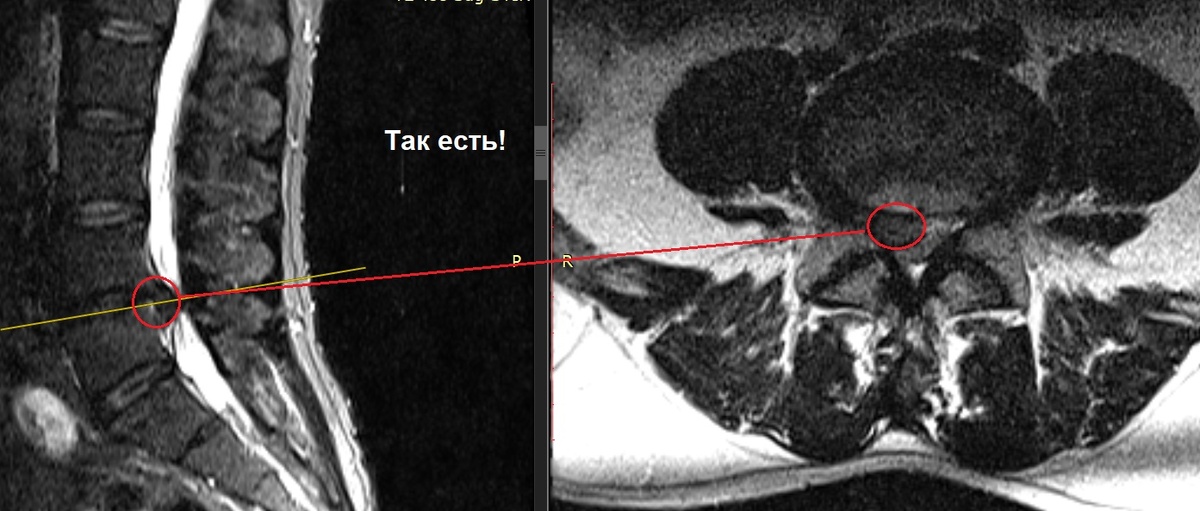

— Вот так есть!

Грыжа диска LIV-V, парафораминальная (со смещением от от центра) вправо, с признаками компрессии корешка L:4 на этом уровне.

­­— А вот так должно быть!

Срез на уровне LIII-IV - абсолютная возрастная норма (незначительные дегенеративные изменения межпозвонкового диска)